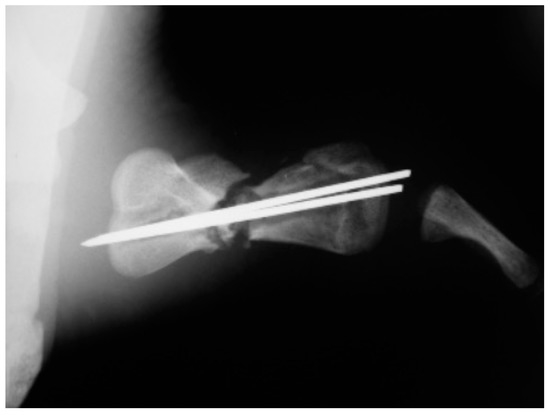

A juvenile sea turtle was presented to the Sea Turtle Clinic (STC) of Veterinary Medicine Department of the University of Bari with an entanglement lesion affecting the right front flipper. On admission, the sea turtle was measured and underwent a complete physical examination; curved carapace length (CCL) from notch to tip ranged 41 cm, curved carapace width (CCW) was 37 cm, and the weight was 18 Kg. The turtle appeared responsive but weak and dehydrated. Clinical evaluation of the musculoskeletal system performed out of the water showed swelling of the right front flipper and evidence of pain on deep palpation of the respective brachial muscle. A reduction in the right front flipper’s range of motion was observed when the turtle was examined in the water. Radiographic assessment, in dorso-ventral (D-V) and Caudo-Cranial (C-C) projections, indicated detachment of the distal epiphysis of the humerus, compatible with a type II Salter-Harris fracture, together with a transverse diaphyseal fracture (Figure 1). The turtle underwent general anesthesia, and the craniodorsal access to the humeral diaphysis was performed. The epiphyseal fracture was reduced by closed surgery and fixed using two crossed 2.5 mm Kirschner pins, introduced backward from the distal stump and brought out through the hyperflexed humerus-radio-ulnar joint. The same pins used to fix the epiphyseal fracture were inserted into the proximal stump to fix the diaphyseal fracture. After checking the stability of the fractures reductions, the surgically sectioned soft tissues were reconstructed, and post-operative radiographs were performed. Follow-up was performed after the surgery at 2, 4, 12, 16, and 24 months, when the turtle was released at sea. Three months after its release at sea, the turtle was caught dead in a fishing net at a depth of 40 m. To determine the evolution of bone repair from turtle release to death, the right humerus was removed for histological and histomorphometry analyses. Immediately after explant, the humerus was fixed in 4% buffered paraformaldehyde, dehydrated in ethanol, and embedded in methylmetacrylate. Serial cross sections, 750 µm thick, were cut at both the diaphyseal and epiphyseal fracture gaps using a circular diamond-bladed saw (Gillings Hamco) and were ground to a thickness of 100 µm. Sections were placed on a specimen holder and microradiographed using a microradiograph (Constant 1-K, Ital Structures, Italy) at a prefixed distance from the X- ray generator of 9.5 cm. X-ray exposure was set up at 8 kV and 14 mA. Contact microradiographs were obtained on Kodak high-resolution film (SO 343, Eastman Kodak Co., Rochester, NY, USA), developed with Kodak HC-110, fixed in Kodak UNIFIX, washed in distilled water and then airdried at room temperature. Sections were subsequently stained with 1% toluidine blue (pH 3.7) for mineralized tissue. Four separate levels were selected, three belonging to the mid-diaphyseal fracture gap, and one level to the epiphyseal fracture gap: the first and the fourth levels corresponded to the proximal and distal part of the callus, respectively, and the second and third levels to the center of the fracture (Figure 2). As a control, the left humerus, which had never been fractured, was processed with the same procedure. On the stained sections, using a Nikon DS-5 camera connected to a stereomicroscope (SMZ800, Nikon Europe B.V., Amstelveen, The Netherlands) and a DS camera control unit, the callus extension was measured and the amount of new laid down bone, cartilage, and fibrous tissue, expressed as percentage ratio of the entire section, were evaluated. Histomorphometry was performed using Nis-Elements BR analysis software (Nikon Europe B.V.).

The post-operative radiographic examination confirmed the correct reduction of the diaphyseal fracture, bone realignment, and the good fixation of the detached distal epiphyseal stump (Figure 3). Fifty days later, the X-ray follow-up showed persistent stability of the joint and bone sclerosis, near the diaphyseal fracture site. After 70 days, the turtle could swim and move around comfortably; radiographic examination showed a better filling of the diaphyseal fracture line and almost complete repair of the epiphysis (Figure 4). Four months after surgery, the animal was in good general condition and had recovered the right front flipper’s normal function. Radiography showed a complete repair of the epiphyseal fracture and remodeling of the normal bone architecture, while the diaphyseal fracture still lacked unifying bone callus tissue (Figure 5). After one year, the flipper showed complete clinical recovery without signs of pain, and radiologically the fracture site was fixed, showing signs of remodeling of the fracture stumps, areas of thickened fibrous tissue, but still no appreciable unifying bone callus (Figure 6a). The good positioning and tightness of the means of fixation were radiologically confirmed, but the surrounding bone reabsorption and decalcification processes were evident. Removal of the intramedullary pins was deemed necessary. Radiograms performed after removal of the pins showed the presence of calcified sites within the tissue interposed between the two bone stumps (Figure 6b). Two years after the procedure, radiographic follow-up demonstrated a better filling of the fracture line and further remodeling of the stump margins (Figure 7).

Figure 1. Caudocranial radiograph of the anterior right flipper showing transverse diaphyseal and the type II Salter-Harris fractures.

Figure 3. Caudocranial radiograph of the anterior right flipper: postoperative follow up examination.

Animals 13 00376 g003

Figure 4. Two-month follow-up performed in caudocranial view of the anterior right flipper showing the filling of the diaphyseal fracture line.

Animals 13 00376 g004

Figure 5. Postoperative checkup at four month: Caudocranial view of the anterior right flipper showed a complete repair of the epiphyseal fracture while the diaphyseal fracture still lacked unifying callus tissue.

Animals 13 00376 g005

Figure 6. Radiographic examination at 12 months before (a) and after (b) removal of the synthesis methods (Caudocranial view): remodeling of fracture stumps, areas of thickened fibrous tissue, but still no appreciable unifying callus.

Animals 13 00376 g006

Figure 7. Twenty-four-month follow-up (caudocranial view) demonstrating a better filling of the fracture line and further remodeling of the stump margins.